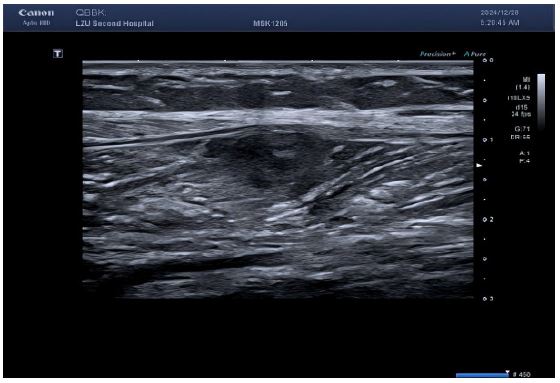

Figure 1: Multiple echogenic areas were detected in the muscle layer of the left medial calf, all with regular morphology, clear borders, and heterogeneous internal echogenicity.

Lower limb ultrasound: Detected a hypoechoic lesion within the intermuscular space of the right calf. Initial impression: Schwannoma suspected; CEUS recommended.

The reasons for the misdiagnosis of this patient as a benign tumor were as follows: (1) The initial diagnostic context involved routine ultrasound without documented extramuscular malignancy, precluding sufficient justification for metastatic suspicion; (2) Sonomorphological mimicry manifested as well-circumscribed, spindle-shaped anechoic foci with smooth margins, distinct hyperechoic capsules, and posterior acoustic enhancement within the calf musculature—features pathognomonic for schwannoma yet discordant with the infiltrative borders characteristic of aggressive malignancies; (3) Vascular analysis (Figure B) revealed sparse punctate vascular signals rather than the abundant internal/peripheral flow or large perforating vessels typical of subcutaneous cancers; (4) CEUS kinetics further reinforced misdiagnosis through arterial-phase peripheral hyper-enhancement with central non-enhancing zones, maintained circumscribed margins, and early washout in adjacent tissues—collectively aligning with classical benign enhancement profiles and creating a compelling illusion of non-malignant pathology.